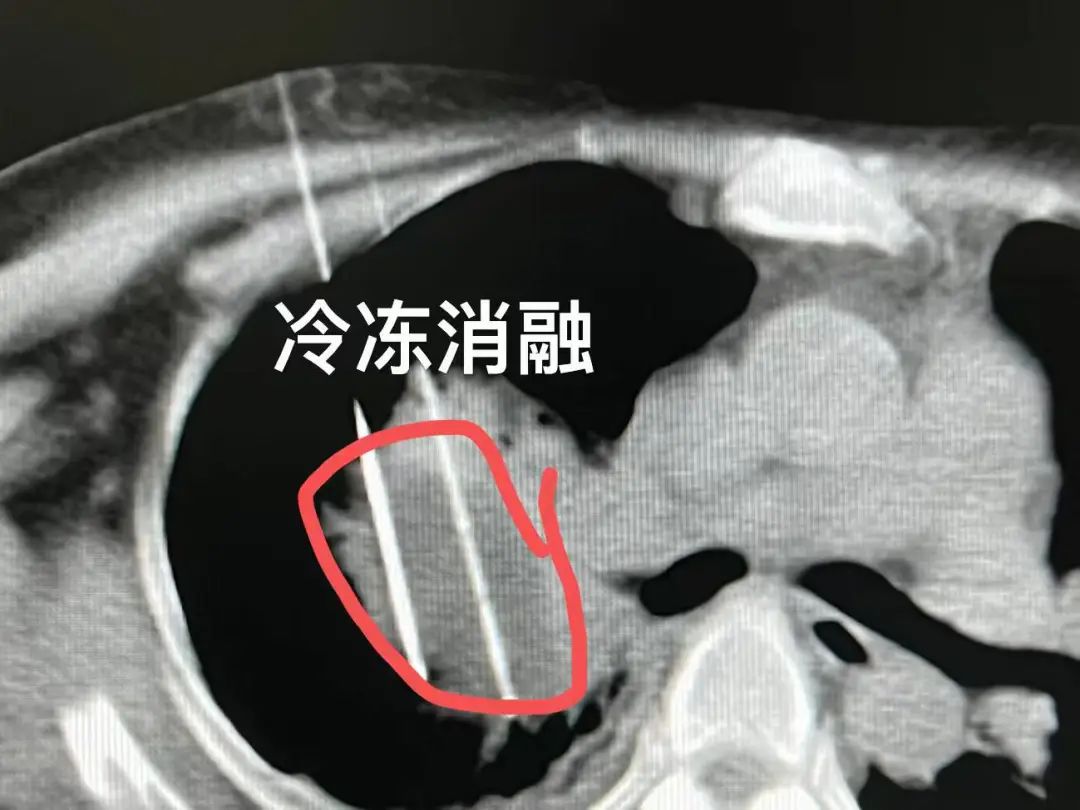

这是一位来自马来西亚的胸腺瘤患者,由于耐受不了全身化疗,把希望都寄托在冷冻消融术上,希望能得到一个一劳永逸的结果。但显然,对于这位晚期患者来说,单一的冷冻消融是无法完全解决问题,若不联合其他疗法,可能会面临复发转移的风险。

又比如这位台湾患者患有肺癌并伴有骨转移,检测到突变基因后开始口服靶向药物。由于局部肿瘤靠近肺门,为此,我采用冷冻消融以防止肿瘤压迫支气管和血管导致肺不张等局部问题。局部治疗与全身治疗是肿瘤治疗的两大手段,两者有效结合可以提高治疗效果。